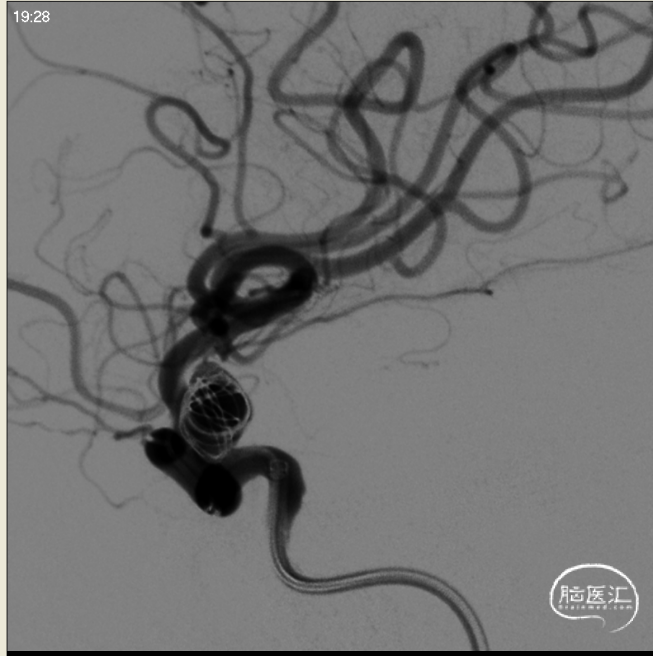

行正侧位造影及3D造影,全身肝素化后路图下将使用经塑形SL10微导管和prowler在0.14微导丝带领下超选进入动脉瘤和载瘤动脉,释放部分4.5*28支架,选用弹簧圈7枚栓塞动脉瘤,充分释放支架,造影复查显示动脉瘤被致密栓塞,载瘤动脉通畅。

成篮圈正位

成篮圈侧位

支架释放正位

支架释放侧位